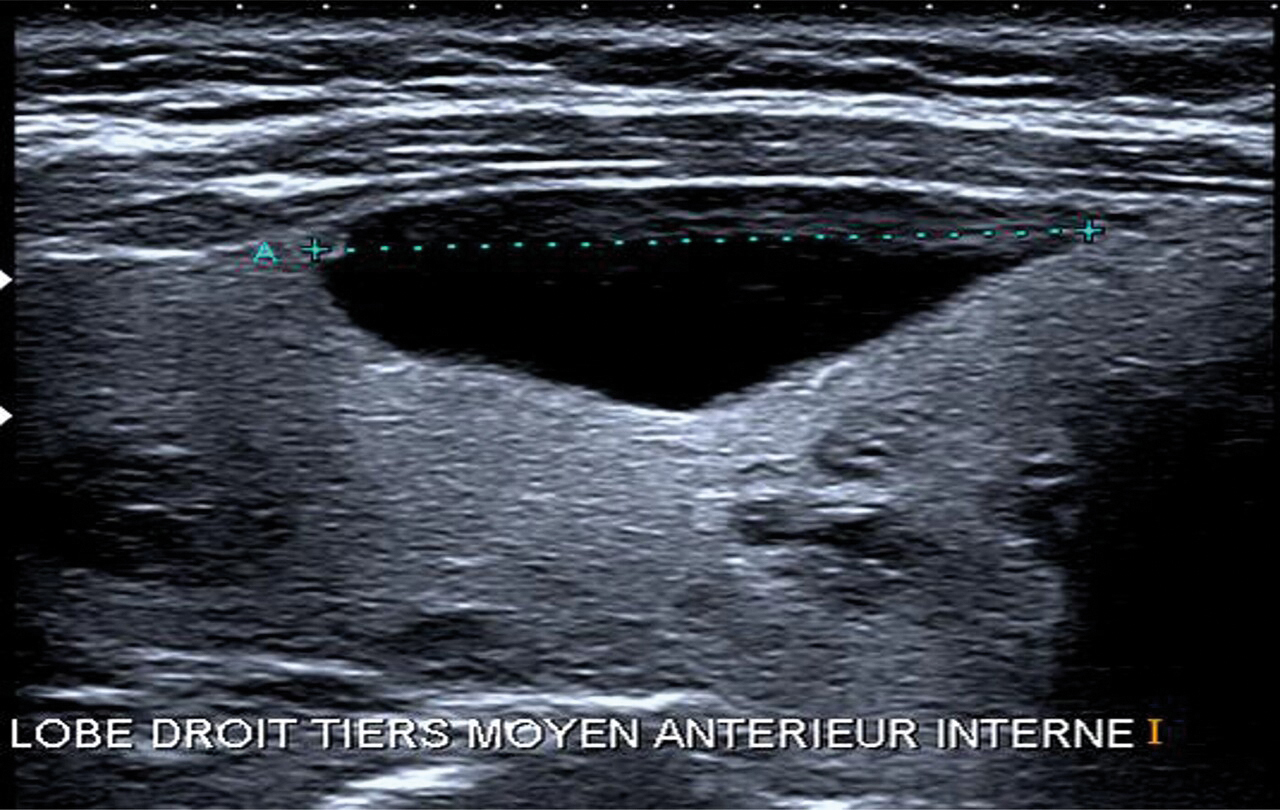

L’échographie thyroïdienne et cervicale est un examen systématique qui fournit des informations essentielles à la suite de la prise en charge : volume de chaque lobe thyroïdien, taille des nodules, classification européenne du système d’imagerie et de données sur la thyroïde (EU-TIRADS)6 et présence d’adénopathie cervicale. La classification radiologique EU-TIRADS évalue le risque de malignité d’un nodule de 2 (fig. 4) à 5 (tableau 1).